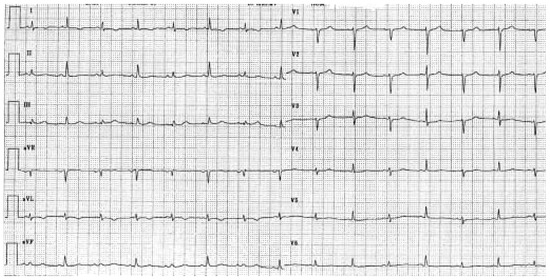

Platypnoe—Orthodeoxie: Eine Seltene Ursache Einer Lageabhängigen Dyspnoe und Arteriellen Hypoxämie

by Urs N. Dürst, Manfred Ritter, Beat Walder and Franz R. Eberli

Cardiovasc. Med. 2005, 8(10), 370; https://doi.org/10.4414/cvm.2005.01130 - 28 Oct 2005

Platypnea—orthodeoxia: a rare cause of positional dyspnea and arterial hypoxaemia. We report a case of an 83-year-old female patient, that developed positional dyspnea after a fall complicated by a thoracic spine compression fracture. In upright position the dyspnea was disabling occurring already with [...] Read more.

Platypnea—orthodeoxia: a rare cause of positional dyspnea and arterial hypoxaemia. We report a case of an 83-year-old female patient, that developed positional dyspnea after a fall complicated by a thoracic spine compression fracture. In upright position the dyspnea was disabling occurring already with normal daily activities, such as dressing. The dyspnea could be relieved by recumbancy. In supine position the patient’s arterial saturation was 94% and decreased to 86% in upright position. Transoesophageal echocardiography revealed an atrial septal defect with bi-directional shunt. The atrial septal defect was closed percutaneously with an Amplatzer-Septal-Occluder® 20 mm. Following the occlusion of the atrial septal defect, arterial oxygen saturation remained stable and the positional dyspnea disappeared. Full article